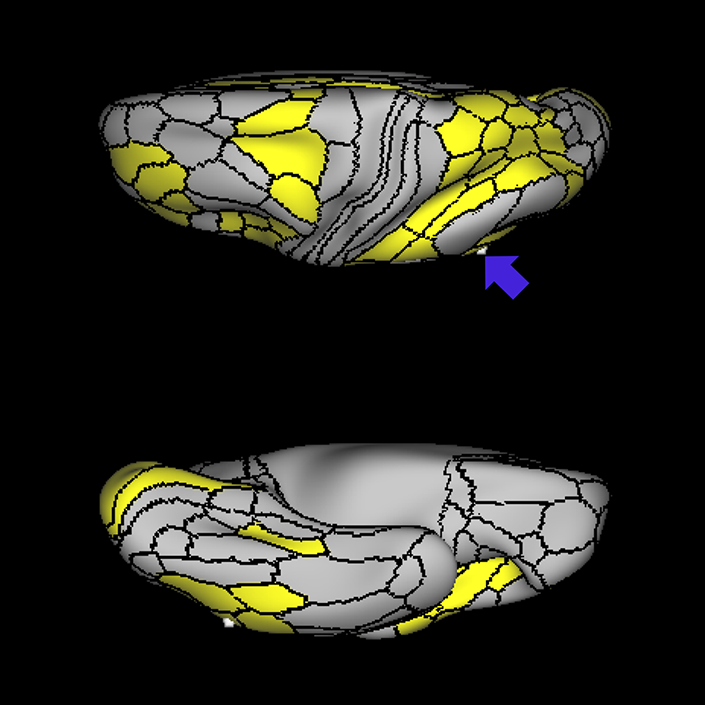

ᐅ SummaryArea 45: part of the inferior frontal gyrus of the lateral frontal lobe. In addition to its known association with Broca's area, is sometimes represented as part of Broca's complex ᐅ Where is it?Area 45 is the lateral surface of pars triangularis of the IFG. ᐅ What are its borders?Area 45 borders area 47L anteriorly and area 44 posteriorly. Its superior edge borders area p47r, IFSa, and IFSp. Its opercular surface is conveniently named FOP5 ᐅ What are its functional connections?Area 45 demonstrates functional connectivity to areas SFL, IFSp, 44, a47r, 47s, 47L, 9a, 9p, 9m, 8AV, and 8BL in the dorsolateral frontal lobe, area 8BM in the medial frontal lobe, area 55b in the premotor areas, areas FOP5, and PSL in the insula-opercular region, areas TGd, TGv, TE1a, STSva, STSdp and STSvp in the temporal lobe, area PGi in the inferior parietal lobe, and area 31pd in the medial parietal lobe. ᐅ What are its white matter connections?Area 45 is structurally connected to the arcuate/SLF and IFOF. However, arcuate/SLF connections are not consistent across individuals. Connections with the arcuate/SLF project posteriorly and wrap around the Sylvian fissure to the middle temporal gyrus to end at TE1p. There are also projections from the arcuate/SLF before it terminates to parcellations A4 and PBelt. IFOF connections travel from 45 through the extreme/external capsule and continue posteriorly through the temporal lobe to end at occipital lobe parcellations V1, V2, V3 and V4. Local short association bundles connect with 44 and FOP4. ᐅ What is known about its function?Area 45, in addition to its known association with Broca's area, is sometimes represented as part of "Broca's complex", including Brodmann Areas 45, 46, 47 and the mesial supplementary motor area of 6, which contribute to a frontal-subcortical circuit. |

A: lateral-medial

B: anterior-posterior

C: superior-inferior

DTI image |